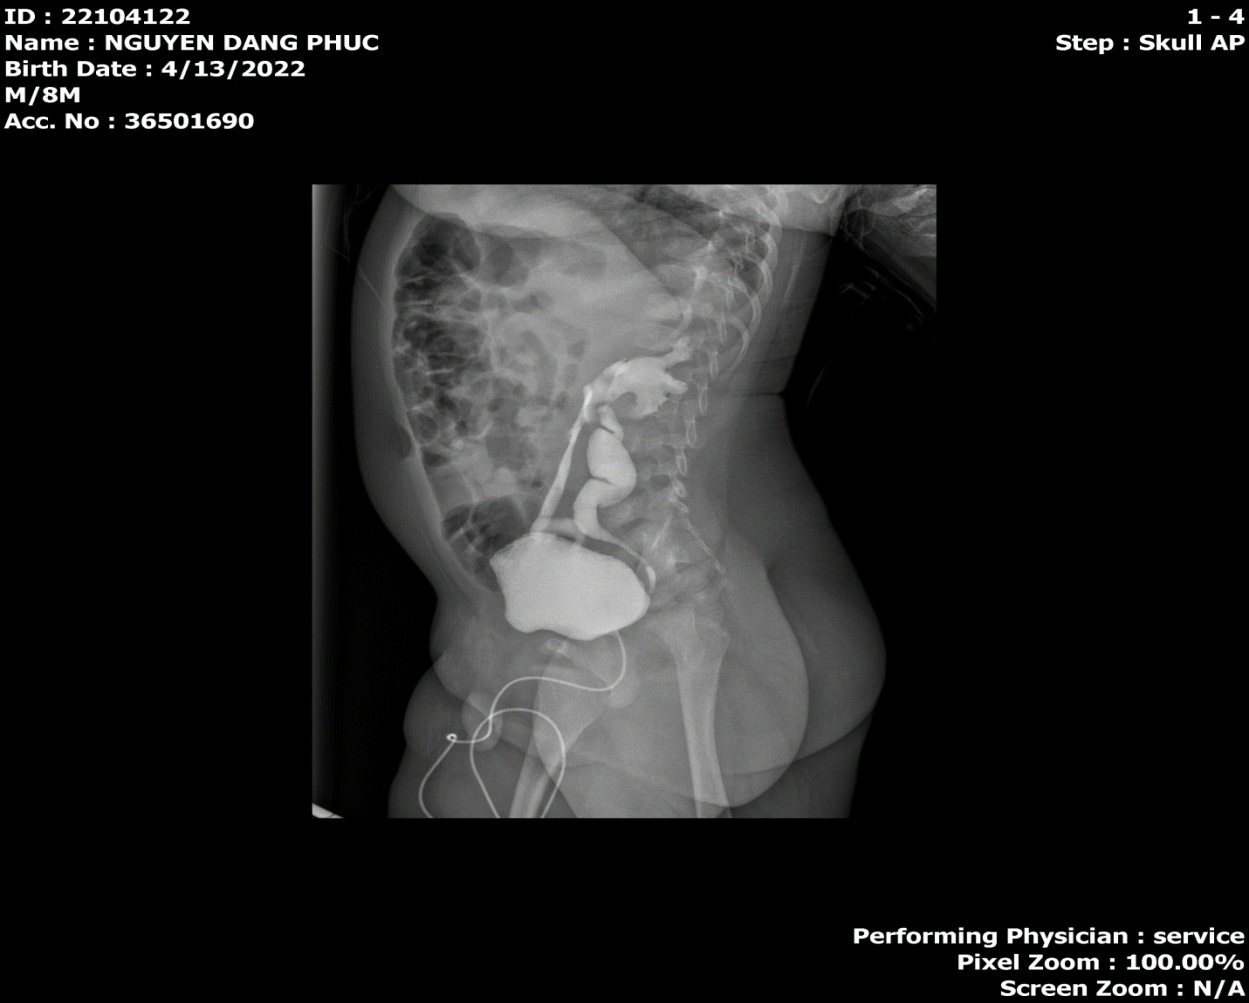

Hình ảnh trào ngược bàng quang niệu quản độ 3